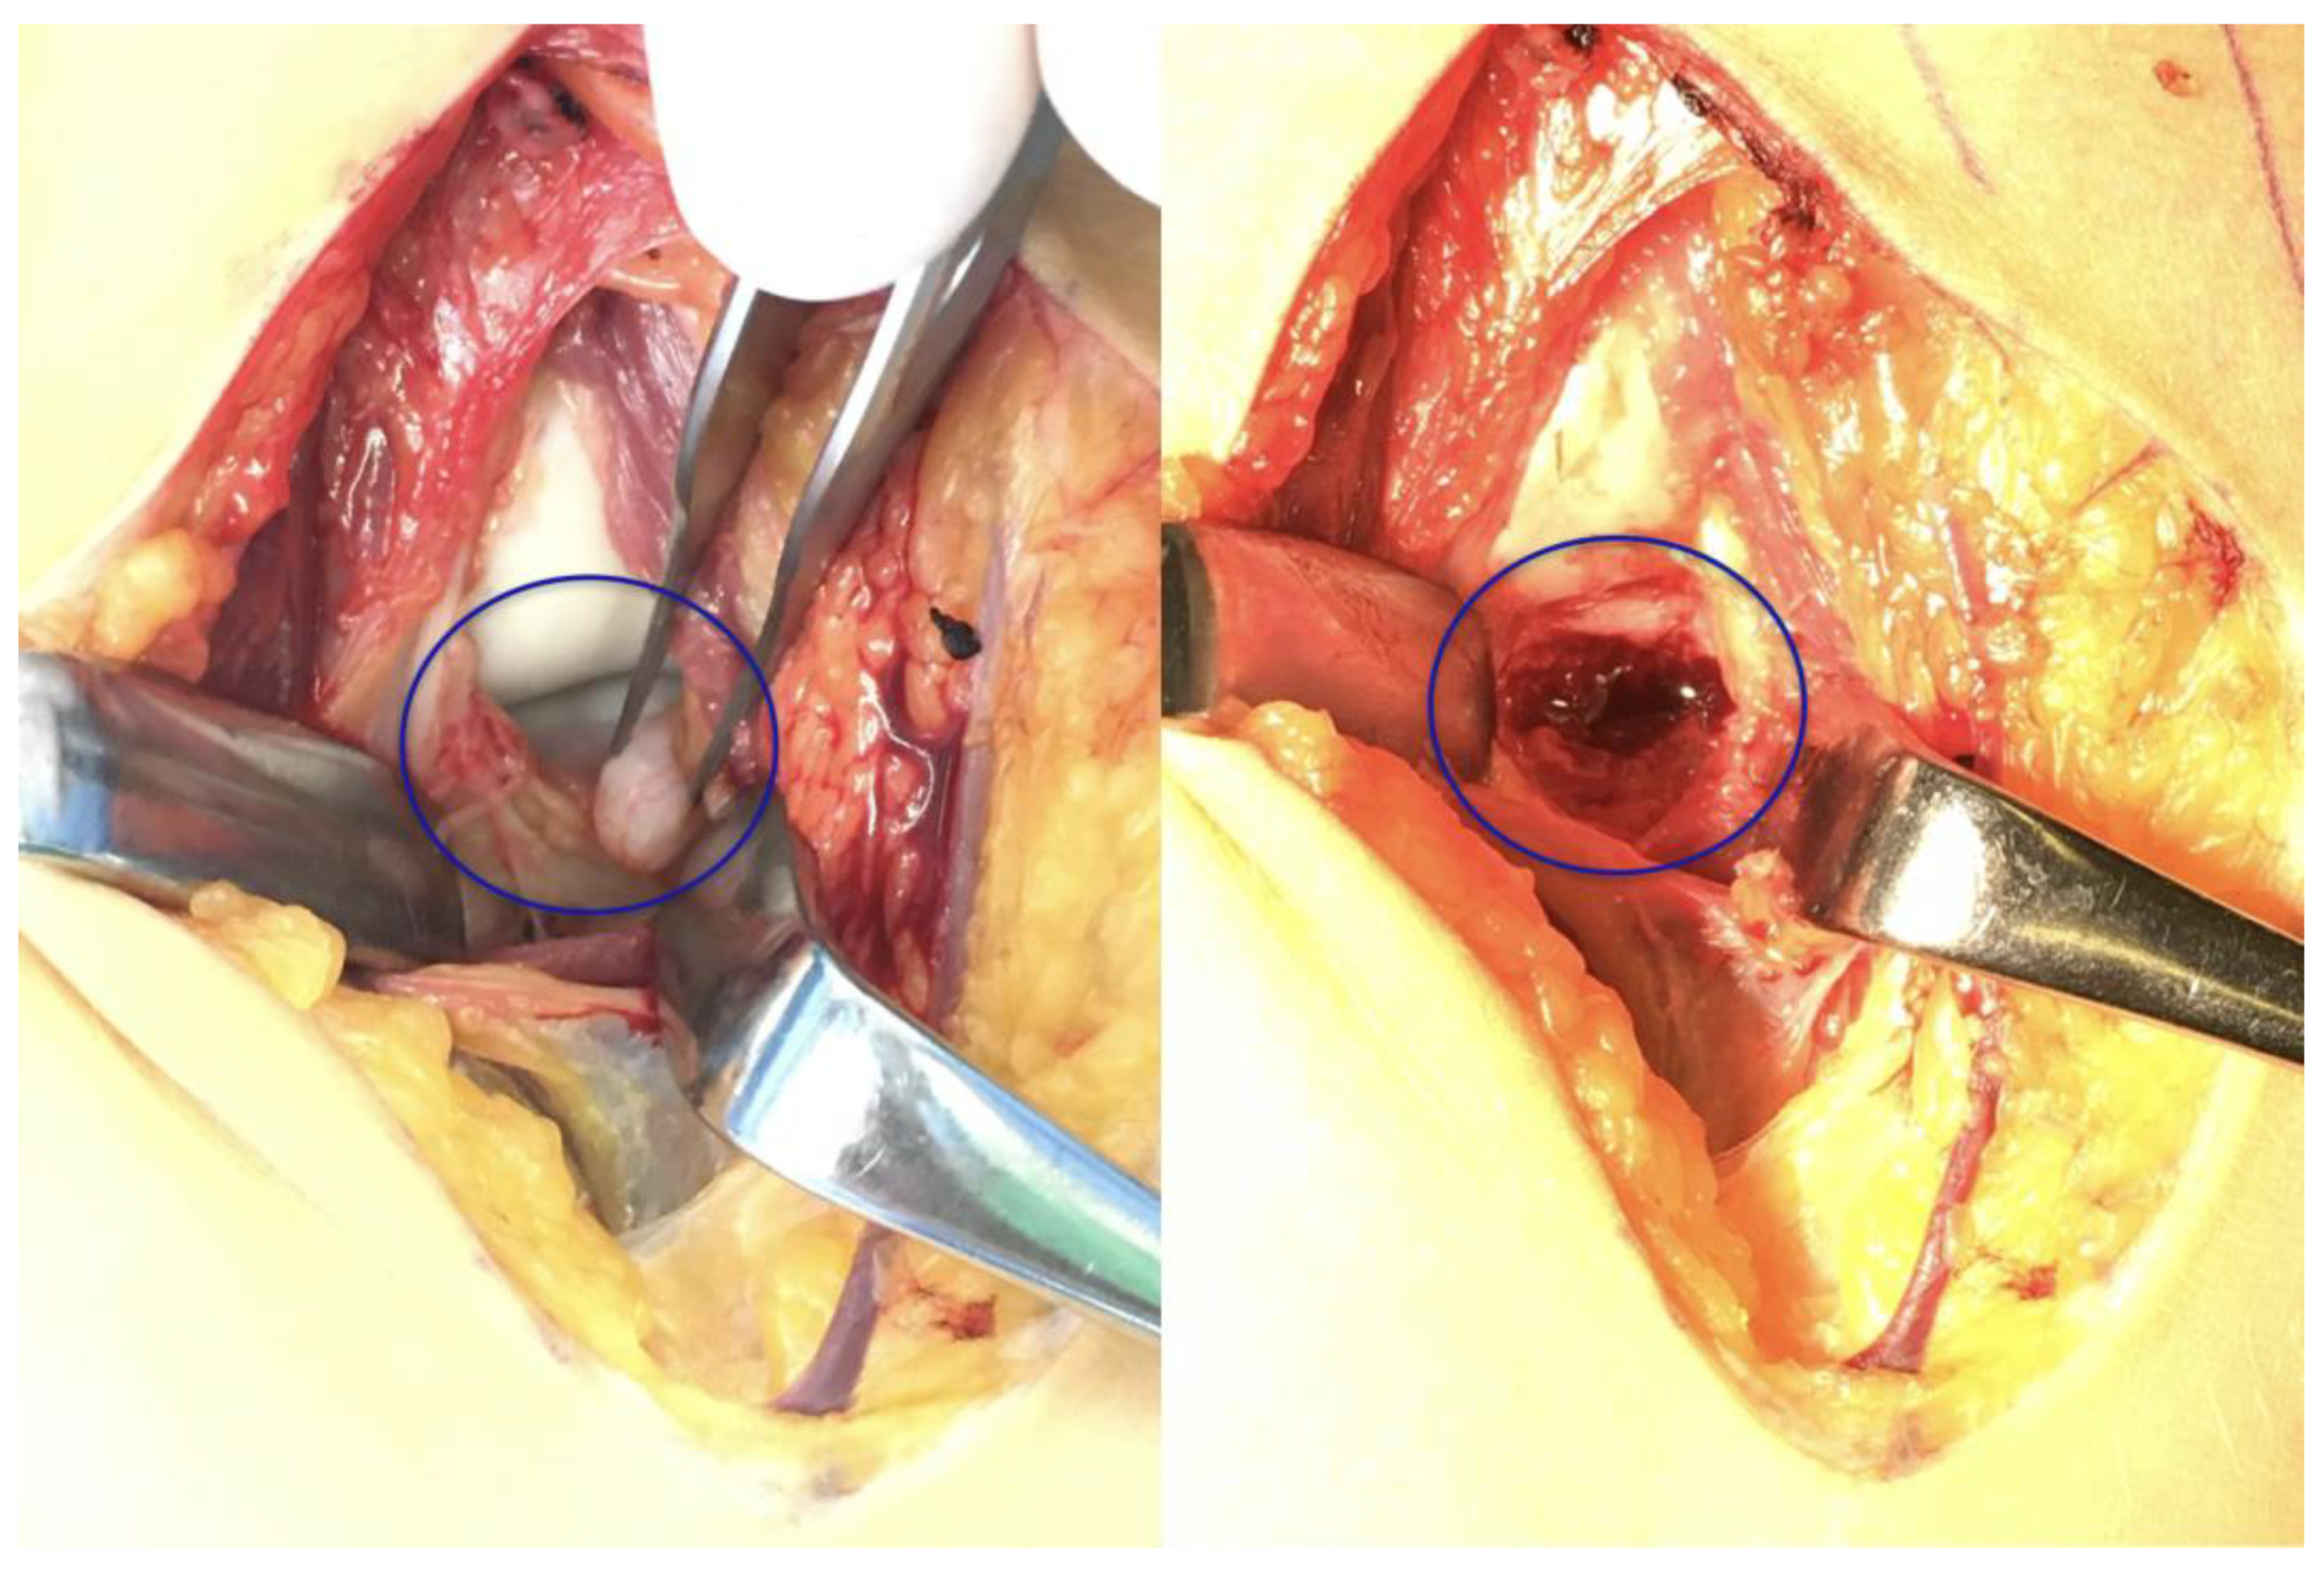

The surgery took place after disinfection and isolation, under general anesthesia, in exsanguinated conditions, and with prophylactic antibiotic protection (1 g Cefazolin) over 90 min. During surgery, the left elbow joint was accessed from an anterior incision, utilizing the modified Henry approach once again. The detached bone fragment was removed and replaced with a corticospongious block obtained from the iliac ala (Figure 7). Preparation of the recipient bed at the coronoid defect site was performed by removing fibrous tissue and refreshing the surface to expose healthy, bleeding cancellous bone. Subsequently, the corticospongiosal autograft was harvested from the ipsilateral iliac ala. The graft was carefully shaped intraoperatively to match the defect dimensions accurately, ensuring an optimal fit to restore the anatomical contour of the coronoid process. This technique aimed to facilitate biological integration and promote rapid healing. The graft was fixed in its final position with two Herbert screws (Johnson & Johnson: Depuy Synthes, Oberdorf, Switzerland). A drain was applied, and after the repair of the subcutaneous layers, the skin was sutured. Following swathing and bandaging, the left upper extremity was immobilized with a long upper limb cast.

Figure 7. Intraoperative images highlighting the separate bone fragment and the defect (blue circle).